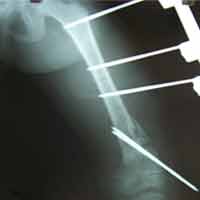

Case:7 Fracture Neck Femur with Implant failure and Re-Fixation with hemi-arthroplasty

Alcoholic Gardener by profession had slipped in bathroom & fell. He sustained fracture neck femur.He was operated with closed reduction & CC Screw fixation under IITV. Two weeks’ post fixation he again fell & sustained fracture in sub trochanteric region. He was treated with Hem-Arthroplasty with Tension band wiring.

Post Fall

Oblique-Post Fall

Lat-Post Fall

Lateral-Post Prosthesis Fall

Post Prosthesis Fall

Post Uninon-3Months